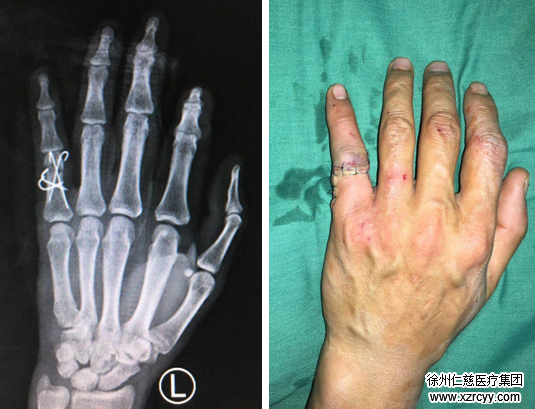

经检查,患者刘刚虎左手小指近节畸形,近节背侧见一横行切口,约3cm,伤口深达骨质,创缘不齐,骨头碎得比较厉害,挫伤污染重,伤口内见肌腱骨折断端外露。胡俊生医生手术小组立即为其清创,固定骨折端,缝合修复拇指伸肌腱及皮肤,并最后进行了外固定。手术进行约2个小时,一切顺利。

我手指因工作受伤骨折,市内二大医院以无病床只简单包扎,拒之门外,只好把侥幸心情寄到必威官方首页官网betway。时已黄昏,医生已要下班,手外科四区胡俊生主任、孔维康医生看此情景,二话没讲,立即开通绿色通道,安排护理人员快速送做X光线,化验检查。确定无明显手术禁忌症后,急把我送手外科四病区手术室。胡主任、孔医生已早等候,做好手术的准备。